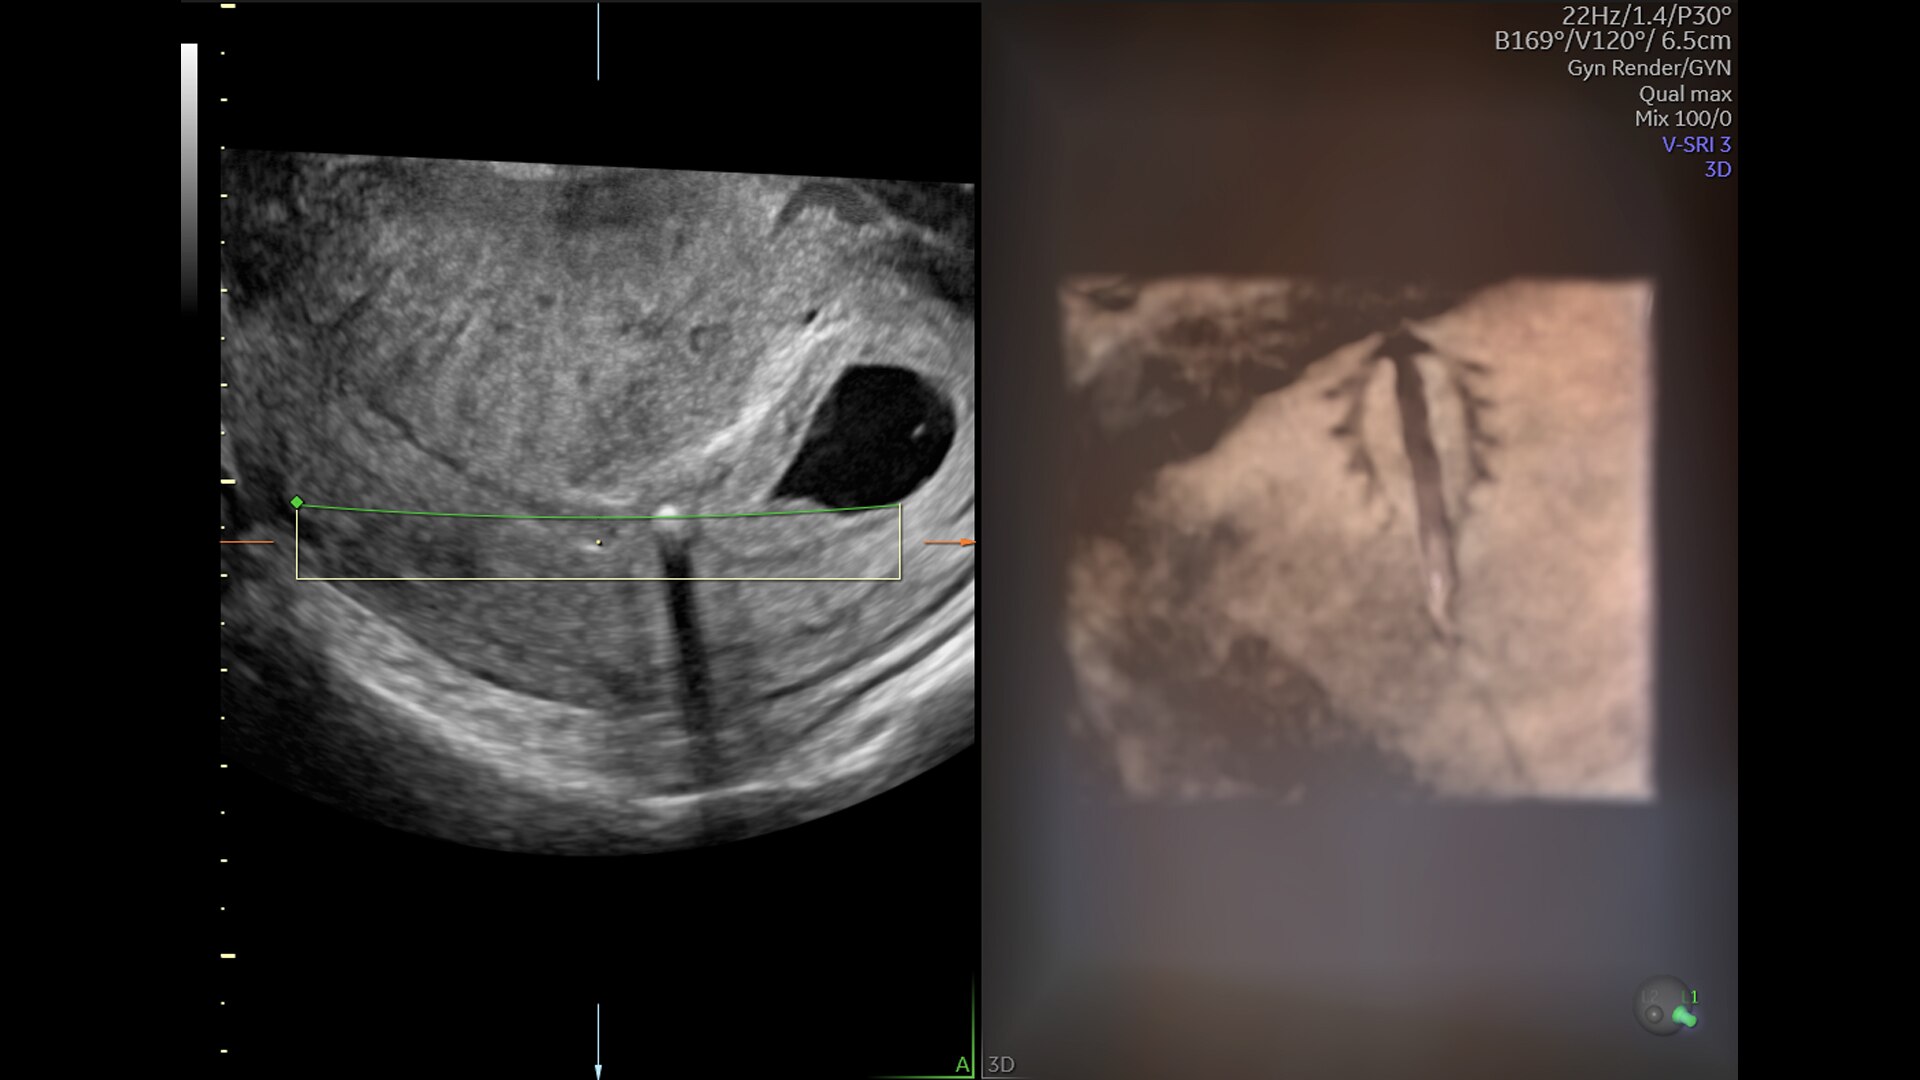

Complex cases come with enough uncertainty. That's why the Voluson Expert 22 is specifically designed for in-depth assessment of complicated anatomy — with pioneering first trimester, fetal cardiac, gynecological, and other pivotal technologies that focus on early detection and intervention.

First Trimester Exams

Perform detailed exams with high-resolution for early insights to fetal health